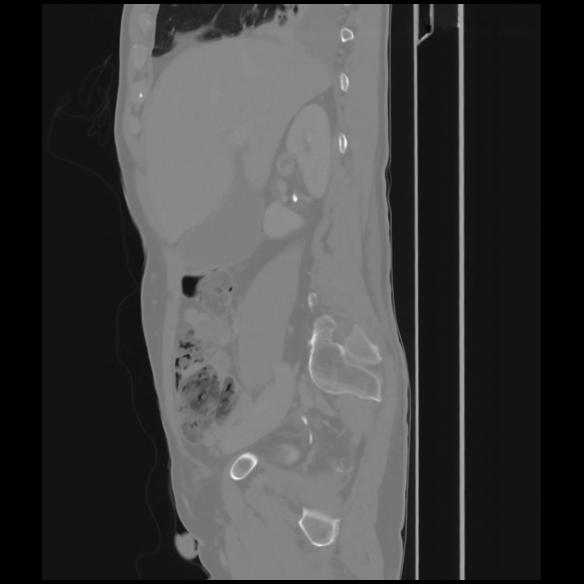

7 CUERPO,CE,Sagittal,3.000,CUERPO,Sagittal,